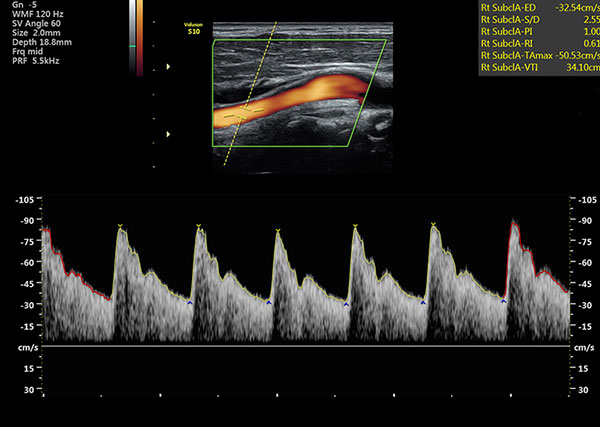

Doppler vascular ultrasound or a color Doppler ultrasound is a special ultrasound technique that allows the physician to see and evaluate blood low through arteries and veins in the abdomen, arms, legs, neck and/or brain (in infants and children) or within various body organs such as the liver or kidneys. Vascular ultrasound produces precise images and measurements of many blood vessels in the body. It can detect diseased vessels and identify a wide variety of changing conditions, enabling the radiologist to make a quick and accurate diagnosis.